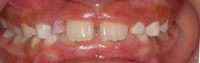

反対咬合

2.かみ合わせが深い場合(かみ合わせたときに上の歯しか見えず下が全く見えない)

過蓋咬合

3.永久歯がまっすぐに出てこない場合

叢生